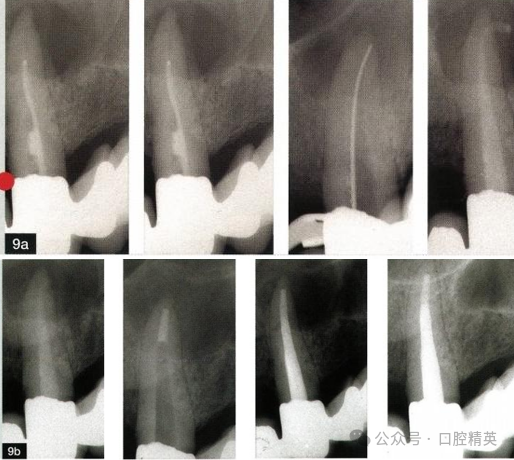

9、一次约诊还是多次约诊完成根管再治疗?